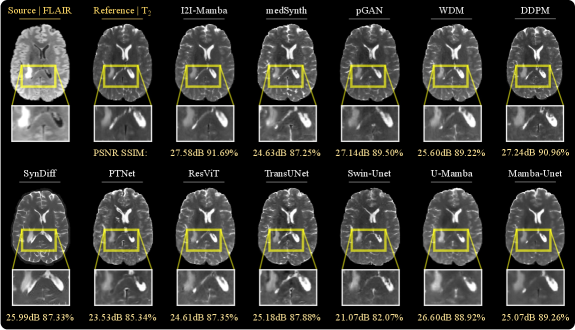

Representative synthetic images are displayed in Fig. 5. Among competing methods, convolutional baselines suffer from residual noise (e.g., pGAN, WDM) or structural degradations (e.g., medSynth); and diffusion baselines suffer from structural inaccuracies in depiction of low-to-moderate contrast tissue signals (e.g., DDPM) and a degree of spatial blur (e.g., SynDiff). Meanwhile, transformer and SSM baselines suffers from spatial smoothing (e.g., ResViT, TransUNet, Swin-Unet, U-Mamba), hypo- or hyper-intense contrast compared to ground truth in regions near bone tissue (e.g., PTNet, U-Mamba), or dark-pixel artifacts (e.g., Swin-Unet, Mamba-Unet). In comparison, I2I-Mamba synthesizes target images with lower artifacts and more accurate delineation of tissue structure and contrast, particularly across diagnostically relevant bone regions. Taken together, these results indicate that I2I-Mamba maintains higher sensitivity to contextual features in multi-modal medical images than baselines, thereby increasing fidelity in imputation of missing modalities.